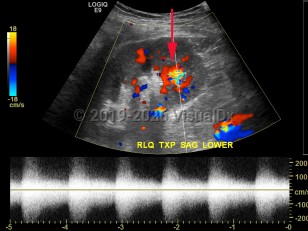

An arteriovenous fistula is an abnormal connection between arteries and veins that may be congenital, surgically induced for hemodialysis or as a rare complication from cardiac catheterization, or acquired from traumatic penetrating injury, infection, or malignancy. Congenital arteriovenous fistulas in the brain may be associated with abnormalities of the vein of Galen. Acquired forms typically occur in lower extremities, and, with long-standing fistulas, symptoms of edema and limb ischemia can occur. Many fistulas repair spontaneously and only require observation, but surgical repair or ultrasound-guided compression is indicated for symptomatic patients.